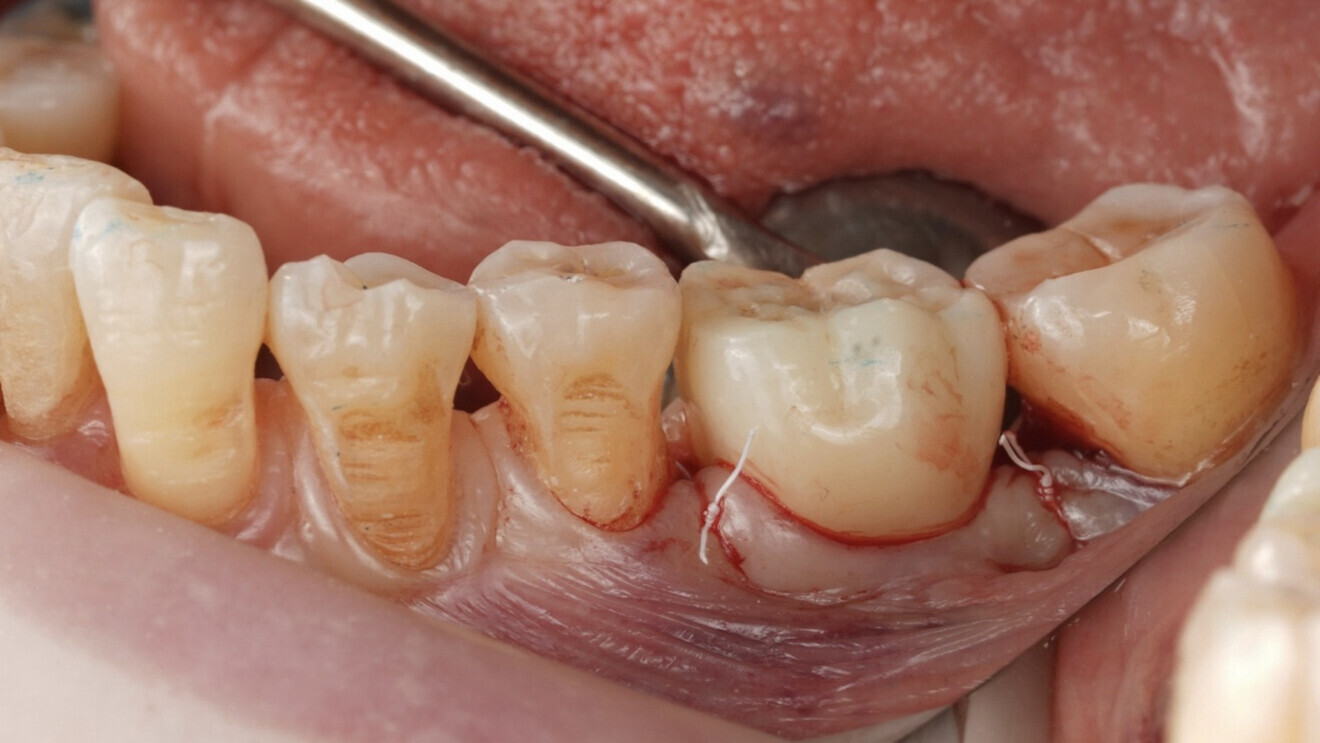

Guided surgery and prosthesis delivery A stereolithographic surgical guide generated from the RealGUIDE planning was used to perform fully guided implant placement under local anaesthesia. A PSK implant was inserted at the site of tooth #36 to a final torque of 50 N cm, confirming sufficient primary stability for immediate restoration.

A straight Ti-base was placed according to the angulation designed in the prosthetic plan. The prefabricated screw-retained crown was seated immediately after implant placement without the need for modification or intra-oral scanning. Clinical verification confirmed excellent marginal adaptation and passive fit, both visually and radiographically. Minimal occlusal adjustment was required, and the crown was permanently screwed in place. The screw access hole was sealed with PTFE and composite resin. The patient was discharged with full function and aesthetics restored in the same session.

After implant placement and connection of the Ti-base, the prefabricated crown was directly seated without adjustment. The passive fit was verified clinically and radiographically. Occlusal contacts were evaluated and required minimal to no adjustment, confirming the accuracy of the virtual workflow.

The prosthesis was permanently screwed into place using a calibrated torque wrench, and the screw access hole was sealed with PTFE tape and composite resin (Figs. 13 & 14). After a radiographic check of the treated area (Fig. 15), the patient was discharged with full function restored in a single session and reported high satisfaction with comfort and aesthetics.